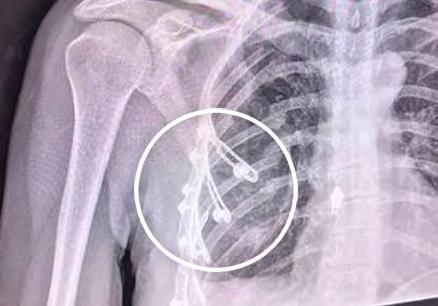

After a devastating cycling accident, elite triathlete Nancy Rehm avoided invasive surgery thanks to RibFix Advantage, a Penn State College of Medicine innovation that stabilizes ribs, reduces pain and speeds healing. Nine months later, she competed for Team USA. Once a research question, the RibFix Advantage System is the first FDA-cleared intrathoracic rib fixation system for less invasive rib repair and is now transforming trauma care worldwide.

Randy Haluck, MD, professor and vice chair for technology, Department of Surgery at Penn State Health Milton S. Hershey Medical Center

Peter Dillon, MD, former chair of the Department of Surgery and vice dean for clinical affairs at Penn State College of Medicine, and executive vice president and chief clinical officer at Penn State Health

Barry Fell, biomedical engineer at Penn State College of Medicine

Donald Mackay, MD, former interim chair of surgery at Penn State Health Milton S. Hershey Medical Center